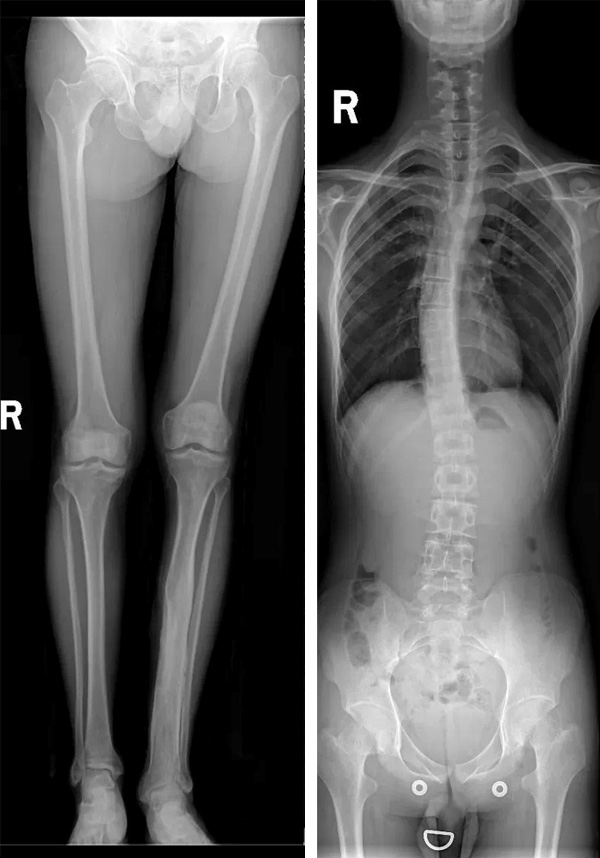

玉中影像檢查再升級(jí)—— 全脊柱及雙下肢全長拼接攝影系統(tǒng)投入使用

近日,玉溪市中醫(yī)醫(yī)院放射科島津C200第五代動(dòng)態(tài)大平板透視攝影系統(tǒng)投入使用,該設(shè)備可開展全脊柱、雙下肢全長檢查。高清攝影、快速診斷、及時(shí)治療,實(shí)現(xiàn)了全脊柱、雙下肢全長檢查的“無縫拼接”,是脊柱側(cè)彎和下肢畸形等骨科疾病術(shù)前術(shù)后X線檢查的首選方法。

放射科主任吉德磊介紹:“以前拍片子需要好長時(shí)間,需多次擺位。由于平板探測(cè)器最大規(guī)格一般只有43cm左右,而脊柱和下肢全長一般超過了這個(gè)長度,現(xiàn)采用新系統(tǒng)實(shí)現(xiàn)全脊柱及雙下肢全長X線攝片,能直觀的顯示全脊柱、雙下肢全長的整體形態(tài),在一張照片上可獲得較清晰、完整的全景圖像顯示,并可進(jìn)行相關(guān)長度測(cè)量、角度測(cè)量等應(yīng)用。”

常規(guī)DR不能一次性完成全脊柱或全下肢X光影像拍攝,需分別拍攝頸椎、胸椎、腰椎、骶尾椎的X光片,只能觀察到局部的側(cè)彎情況,看不到三者之間的連續(xù)性,增加了這類疾病的診治難度。

市中醫(yī)醫(yī)院放射科這臺(tái)高端懸吊DR具有千萬級(jí)像素,利用其特有的“無縫拼接”技術(shù),可獲得一幅完整的全脊柱和全下肢影像,為臨床在脊柱側(cè)彎畸形和下肢骨關(guān)節(jié)病變?cè)\斷、治療方案制定及術(shù)后復(fù)查提供精準(zhǔn)的測(cè)量。

1、判斷下肢力線,主要用于膝關(guān)節(jié)內(nèi)外翻畸形的測(cè)量,能比較準(zhǔn)確地反應(yīng)骨結(jié)構(gòu)異常和軟組織不平衡對(duì)膝關(guān)節(jié)內(nèi)外翻的最終影響。對(duì)膝關(guān)節(jié)置換的X線評(píng)估尤為重要。

01、可以精確測(cè)量雙下肢的長度;

02、可以更好地判斷下肢力線和解剖學(xué)角度;